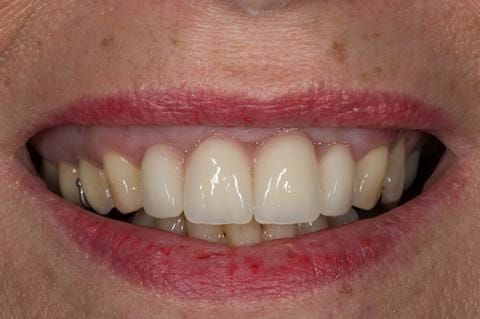

- High smile line showing gum above gingival zeniths of upper front teeth when smiling. Aesthetic failure of the upper four incisors with inflammation of the gingivae and mis-match of the gingival zenith levels.

- Extract the upper 2-2 teeth and replace with an interim acrylic based partial denture. Reline the interim denture over 9 - 12 months, replacing with a definitive cobalt chromium based partial denture. The definitive denture would ideally be designed as an occlusal protective splint to reduce the the potential for mechanical wear and breakages of the moderately/heavily restored maxillary dentition. In addition, should further upper teeth require extraction they could be added on to the denture cobalt chromium framework - therefore a new prosthesis would not be required as future teeth are lost. This option would produce an excellent aesthetic outcome. This is the option the patient chose to have.

Following consultation and second discussion appointment the patient chose to have option 3 namely, a maxillary cobalt chromium based partial denture/protective occlusal splint. The clinical situation and treatment process is shown in detail below with photographs. The patient was successfully rehabilitated with this and her quality of life considerably improved. The clinical work was provided by Finlay and the technical work by Rowan.